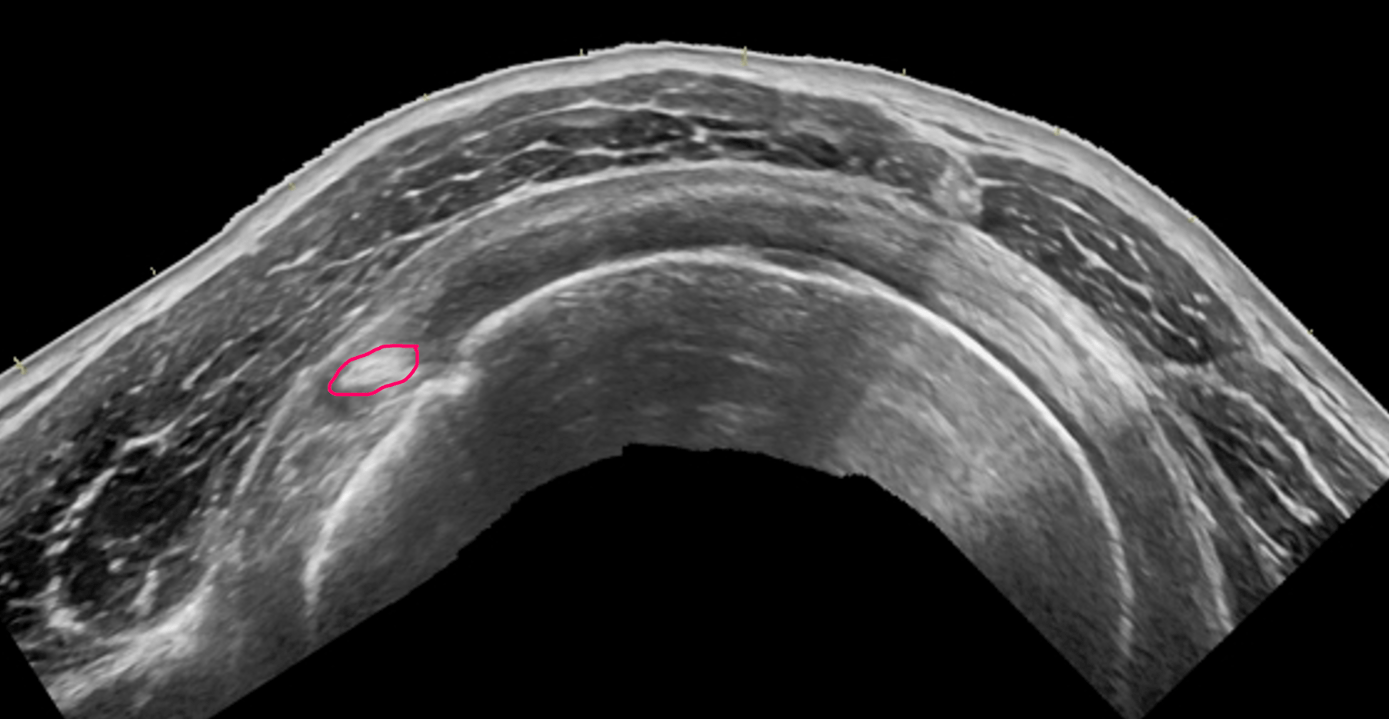

A defect touching a bursal or articular surface but not both.

What is a partial thickness tear?